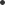

Slika 17

90 % svih operativnih zahvata ugradnje umjetnog kuka tzv. totalne endoproteze ( slika 17. ) je posljedica kranje faze OA kuka ili težih oblika OA kada je zglobna hrskavica propala do te mjere da je došlo do direktnog trenja kost o kost. Riječ je o uspješnoj ortopedskoj proceduri koja donosi smirivanje tegoba u slučajevima konzervativno liječenje ne pokaže ( ne pruži ) rezultat